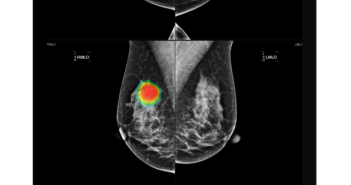

#루닛 이 최근 #홍콩 및 #몽골대형병원 에 #AI유방암검진솔루션 공급 계약을 체결했다. 이번 계약에 따라 루닛은 홍콩 영상센터인 #HKWI병원 과 #몽골국립암센터 및 Breast Clinic of Ulaanbaatar에 #유방촬영술 #AI영상분석솔루션 #루닛인사이트…